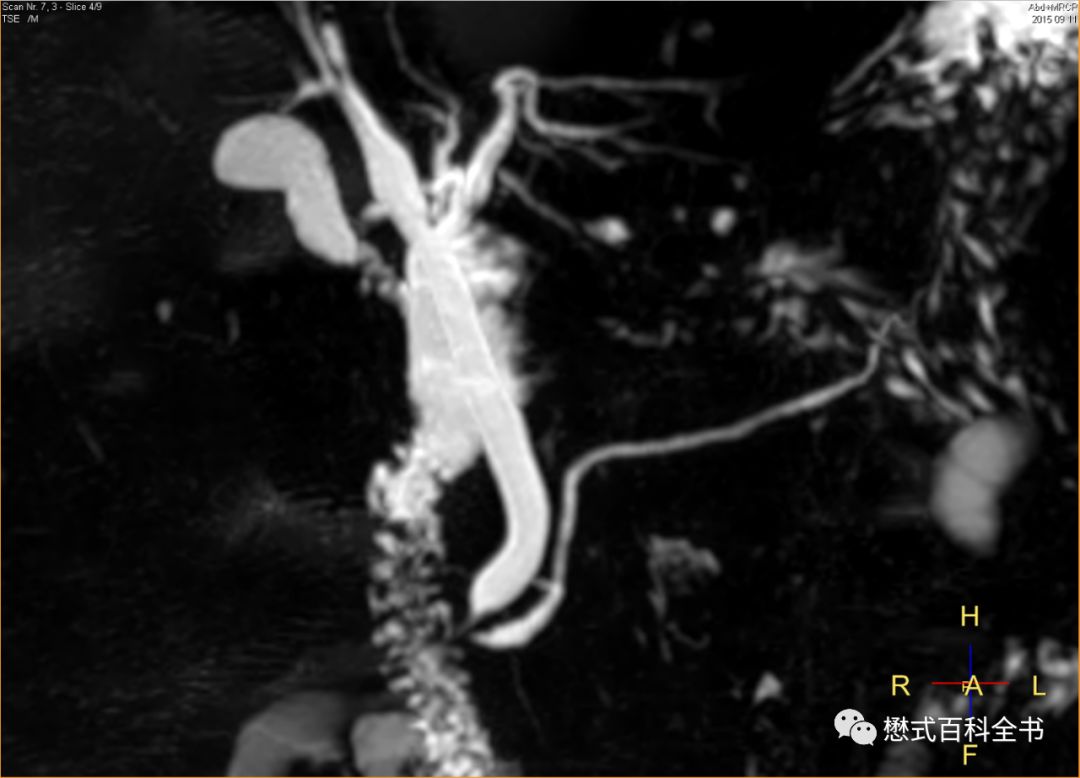

图9:MRCP注意看图中标记的线

有时候,我们组MRCP经常能看到一根比较亮的线竖着穿过胰管。有老师认为是伪影,有老师认为是其他结构。看了一些文献,有的说这个是淋巴管,扫描MRCP出现这个的概率不多。还有文献说和人种有关系,貌似中国人出现这个多。这个位置看着是胸导管?(我们专门有针对胸导管成像的序列,效果非常好)对于这个问题,我也没有过多研究,看看老师们有什么高见,可以留言。